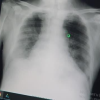

SAMSUN - Enfeksiyon Hastalıkları ve Klinik Mikrobiyoloji Uzmanı Dr. Nurullah Dikmen, omicron varyantını virüsün biteceğini gösteren bir 'müjde' gibi gördüklerini, omicronlu hastaların delta varyantlı hastalara göre hastalığı ayakta geçirdiğini söyledi. Dünyaya yayıldığı gibi Türkiye'de de hızlı bir yayılım gösteren omicron, uzmanlar tarafından müjde olarak değerlendiriliyor. Diğer küresel varyantlarda olduğu gibi Kovid-19'un da 2 yılı aşkın bir süre sonra sona ermesini öngören Medicana İnternational Samsun Hastanesi Enfeksiyon Hastalıkları ve Klinik Mikrobiyoloji Uzmanı Dr. Nurullah Dikmen, birkaç ay içerisinde pandeminin sona ermesini umduklarını söyledi. Omicronda acile başvurma oranlarının diğer varyantlara göre yüzde 10 azaldığını, hastaneye yatma riskinin 2 kat düştüğünü ve solunum cihazına bağlanma oranının da yüzde 802e kadar düştüğünü dile getiren Uzm. Dr. Dikmen, omicron varyantının delta ve diğer varyantlara göre akciğere tutulum oranının oldukça düşük olduğunu ifade ederek, önemli açıklamalarda bulundu. "Omicronu pandeminin 3-4 ay sonra biteceği 'müjde' gibi algılıyoruz" Kısa bir süre sonra pandeminin sona ermesini beklediklerini dile getiren Uzm. Dr. Nurullah Dikmen, "Şu anda gündemimiz omicron varyantı. Daha önceden yaygın varyant, delta varyantıydı. Delta, omicrona göre daha hasta yapıcı özelliğe sahipti. Buna bir 'müjde' diyebiliriz. Omicron daha hızlı yayılıyor ama hastalandırma oranı oldukça düşük. Bunu 3-4 ay gibi bir sürede pandeminin biteceği müjdesi gibi algılıyoruz. Omicronun en belirgin özellikleri; burun tıkanıklığı, boğaz ağrısı ve hapşırma. Öksürük, bu varyantta deltaya göre daha az görülüyor. Akciğer tutunumu, deltaya göre oldukça düşük. Belirli bir yaş ve alt hastalığı olanları tabi ki omicronda da hastalanabiliyor. Tat alma ve koku kaybının azalması omicronda daha az. Bunların dışında omicronda mide bulantısı, karın ağrısı, gece terlemesi ve bel ağrıları diğer varyantlara göre daha fazla oluyor. Omicron, klinik olarak diğer varyantlara göre daha iyi. Acile başvuru yüzdesi deltada yüzde 15'ken, omicronda bu oran yüzde 5'lere düştü. Hastaneye yatma riski deltada yüzde 4'te oranındayken omicronda ise yüzde 2'ye düştü. Hatta solunum cihazına bağlanma oranı da diğer varyantlara göre yüzde 80'e kadar düşüş var. Yani evde, ayakta geçirilen bir varyant hastalığını görüyoruz. Bulaşıcılığı fazla ama hastalandırıcı özelliği diğer varyantlara göre oldukça az" dedi. "Yaşlılar ve alt hastalığı olanlar omicronu ağır geçirebilir" Yeni varyantın daha az hastalık belirtisi göstermesine rağmen yaşlıların ve alt hastalığı bulunan kişilerin daha dikkatli olması gerektiğini belirten Dr. Dikmen, "Aşılılar için karantina süreleri düştü. Pandemi artık birkaç ay içerinde kalkacak. Normal bir grip ve soğuk algınlığı gibi olup sona erecek. Maske kullanımı önümüzdeki sonbaharda kalkabilir. Uzak Doğu'da başka hastalıklarda bile maske takan var ancak Kovid-19 dolayısıyla birkaç ay sonra maske takmayacağımızı söyleyebiliriz. Her kan grubundan insan kovide yakalanabilir. Bazı hastalar PCR yaptırıyor, bazıları ise yaptırmıyor. Hasta olmadığı halde pozitif olanlar da çıkıyor. Aşı, maske, mesafe ve hijyen kuralına uyarsak bu ara dönemi daha rahat atlayabiliriz. Dünyadaki pandemiler 2 yıldan birkaç ay sonra bitiyor. 100 yılda bir olan pandeminin de birkaç ay içinde kalkacağını umuyoruz. Hastaların çoğu omicronu ayakta geçiriyor ama bu herkesin hastalığı ayakta geçirecek anlamına gelmiyor. Yaşlılar ve alt hastalığı olanlar omicronu ağır geçirebilir. Bağışıklık sistemi düşük olanların daha dikkatli olması konusunda uyarıyoruz" şeklinde konuştu. "Omicronda akciğer tutulması delta varyantına göre oldukça az" Son olarak varyantların akciğer tutulumları hakkında da bilgiler veren Dikmen, şunları söyledi: "Delta varyantına yakalanan hastalarda akciğer tutulumunun daha fazla olduğunu görüyoruz. Omicron varyantına yakalanmış bir hastanın akciğer filmine baktığımızda ise deltaya göre çok az kaldığını görebiliyoruz. Bu da omicron geçiren bir hastanın, delta varyantına yakalanan bir hastaya göre daha rahat nefes aldığını gösteren bir durumdur."